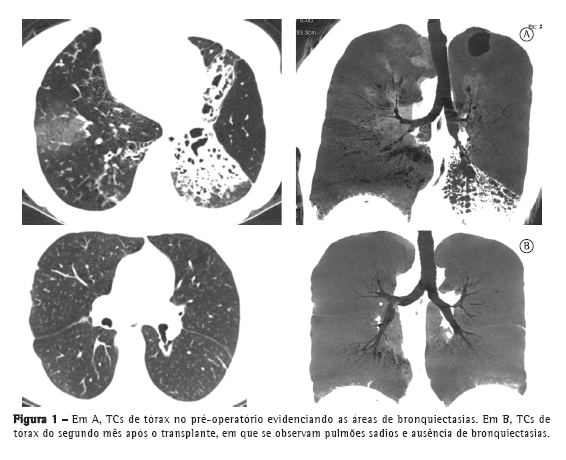

Há 13 anos atendemos uma paciente de 26 anos, portadora de síndrome de Kartagener com história de pneumonia de repetição e bronquiectasias localizadas, refratárias ao tratamento clínico. Estavam indicadas a lobectomia média (à esquerda) e lingulectomia (à direita). A paciente permaneceu assintomática durante 10 anos até o recrudescimento das pneumonias devido a novos focos bronquiectásicos (Figura 1), tendo evoluído com importante comprometimento da função pulmonar, o que demandou o uso contínuo de oxigenoterapia a 7 L/min.

No 2º mês PO, a paciente apresentava VEF1 de 2,05 L (74,3% do previsto) e CVF de 2,45 L (75,4% do previsto). No 6º mês PO, o VEF1 era de 2,27 L (81% do previsto). Até o presente momento (12º mês PO), a paciente apresenta VEF1 de 2,47 L (85% do previsto) e CVF de 2,37 L (82,4% do previsto).